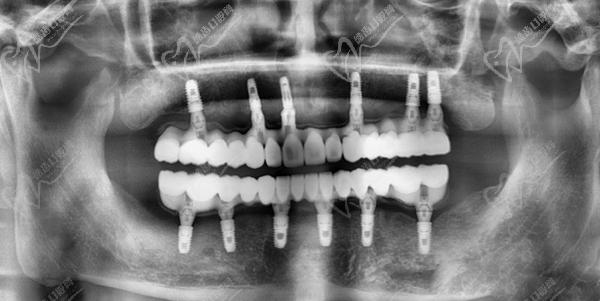

(2)制定手術(shù)方案:根據(jù)口腔檢查的結(jié)果,制定詳細(xì)的數(shù)字化3D模擬手術(shù)方案,包括種植體的數(shù)量、型號選擇、植入位置、深度以及角度等,方案設(shè)計精密度高。

(3)士卓曼半口全口即刻負(fù)重種植技術(shù):瑞士士卓曼種植體可以用于all-on-4/6即刻負(fù)重和穿顴穿翼超高難度種植手術(shù),可以解決一些常規(guī)種植技術(shù)和普通種植體無法解決的問題,提高種植牙的成功比率和患者的生活質(zhì)量。但是,由于這些技術(shù)難度較大,需要醫(yī)生具有豐厚的經(jīng)驗和高超的技術(shù)水平,因此患者需要在選擇醫(yī)生時進(jìn)行充分的調(diào)查和比較。

瑞士士卓曼種植牙的成活率非常高,使用壽命長達(dá)四五十年甚至更長時間,能夠滿足年輕患者的長期需求,以及高齡疑難種植牙患者的種植難題。

不過,具體瑞士士卓曼種植牙的使用壽命取決于多種因素,如患者的口腔衛(wèi)生狀況、咬合力大小、飲食習(xí)慣等。一般來說,瑞士士卓曼種植牙的使用壽命比其他植體品牌使用時間長,能夠滿足患者的長期需求。